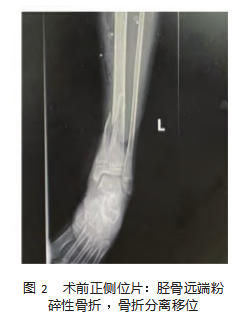

查体:神清,精神良好,问答切题,背入所,查体合作,头胸腹未见异常。左小腿下段见一长度约20cm×3cm不规则疤痕(植皮术后),左足底感觉减退,左足背动脉搏动存在,左小腿下端未见明显畸形,左踝关节及左足肿胀,左踝关节活动受限:背曲0~10度(健侧0~30度),跖屈0~15度(健侧0~50度)。左胫后肌、踇长及趾长屈肌肌力IV级,右下肢未见异常,余无特殊。复阅送检影像学资料显示:2022年9月11日术后三维CT(如图1所示)及术前X线(如图2所示):左胫骨远端粉碎性骨折;同年11月11日DR片显示:骨折线模糊,骨折复位可(如图3所示);2023年3月4日DR片显示:骨折愈合良好,未见明显骨桥形成及明显小腿内外翻畸形。